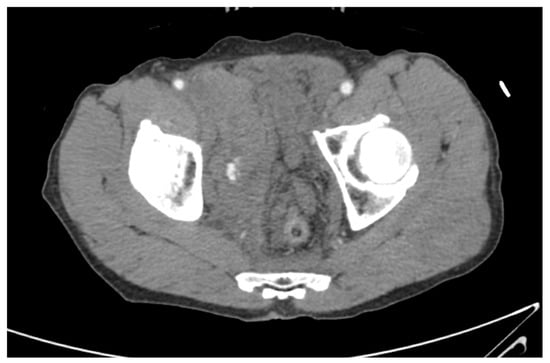

3.4. Details of Patients Who Underwent AE after REBOA